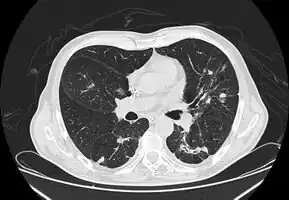

Imaging

Chest X-ray: Nodular shadows both lungs

CT chest: Paracoccidioidomycosis

In the juvenile form, lung abnormalities are shown in high-resolution CT scans of the lungs, whereas in the chronic form plain X-rays may show interstitial and alveolar infiltrates in the central and lower lung fields.[14]